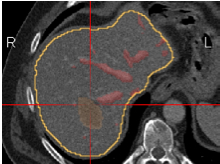

Tumorsegmentierung (halbautomatisch)

Lebertumore bzw. Metastasen lassen sich am Bildschirm meist gut erkennen und können mit wenigen Mausklicks angetastet werden. Pro Tumor ein Mausklick. Anschließend sind die Tumore auch in der 3D-Ansicht deutlich erkennbar.